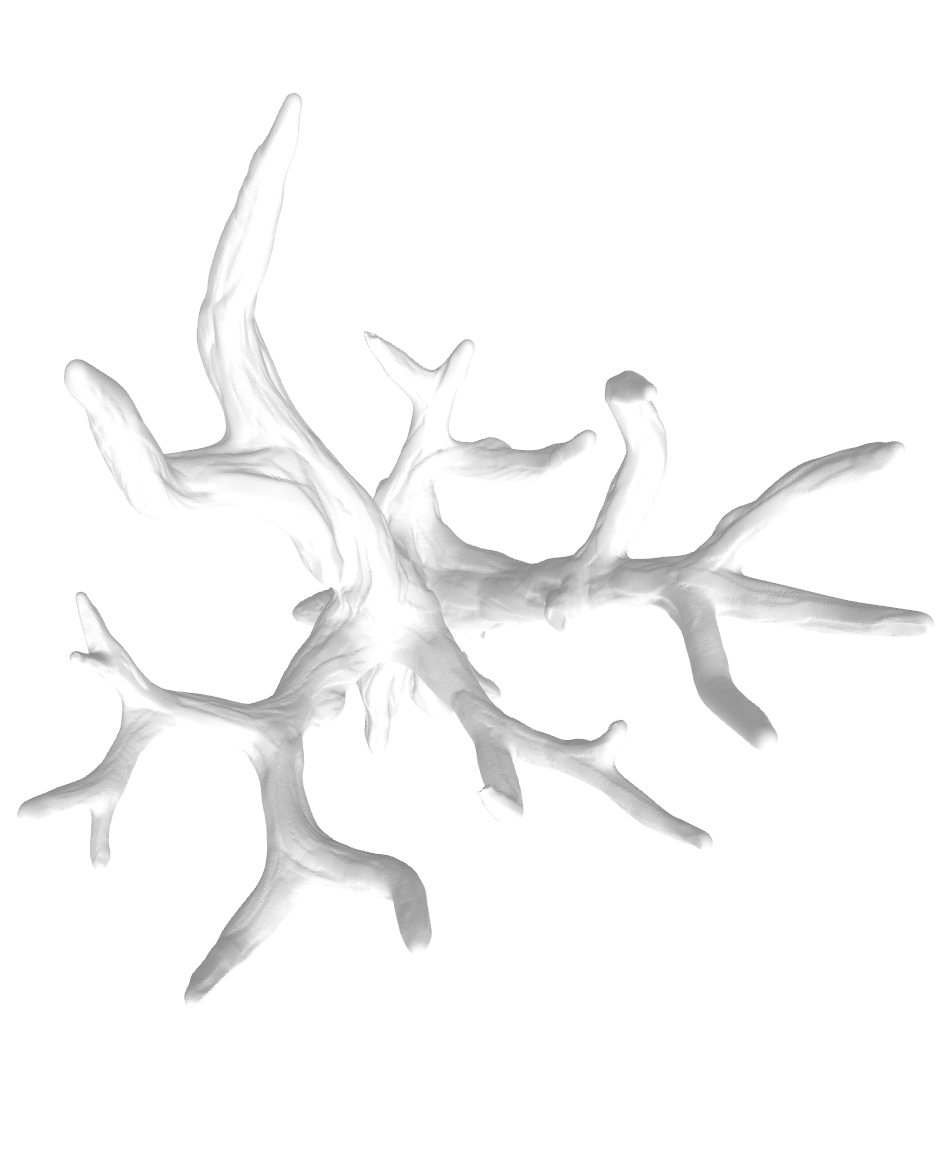

Aryan Gandhi

aav2023rias3681

Jean Hertzberg

Shrey Naresh Solanki